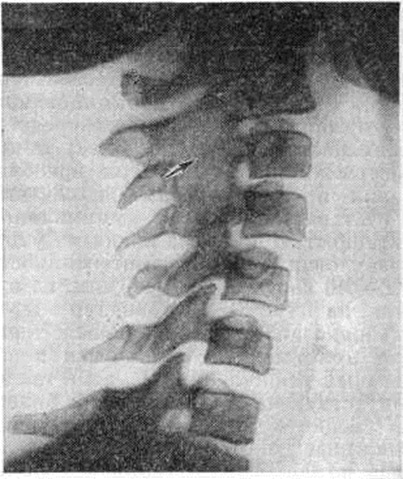

Информация об Ordo Deus Перейти в оглавление сайта

Рис. 11.

Рентгенограмма шейного отдела позвоночника при ювенильном ревматоидном артрите (боковая проекция): стрелкой указан костный анкилоз позвоночных суставов в области III и IV шейных позвонков.

При ювенильном Ревматоидный артрит наблюдаются те же рентгенологическое изменения, что и при Ревматоидный артрит Характерно более частое, чем при Ревматоидный артрит, развитие артрита мелких суставов шейного отдела позвоночника, иногда с исходом в анкилоз (рисунок 11), и нарушения нормального хода развития скелета: ускорение роста трубчатых костей поражённой конечности или, наоборот, недоразвитие отдельных костей (например, нижней челюсти).